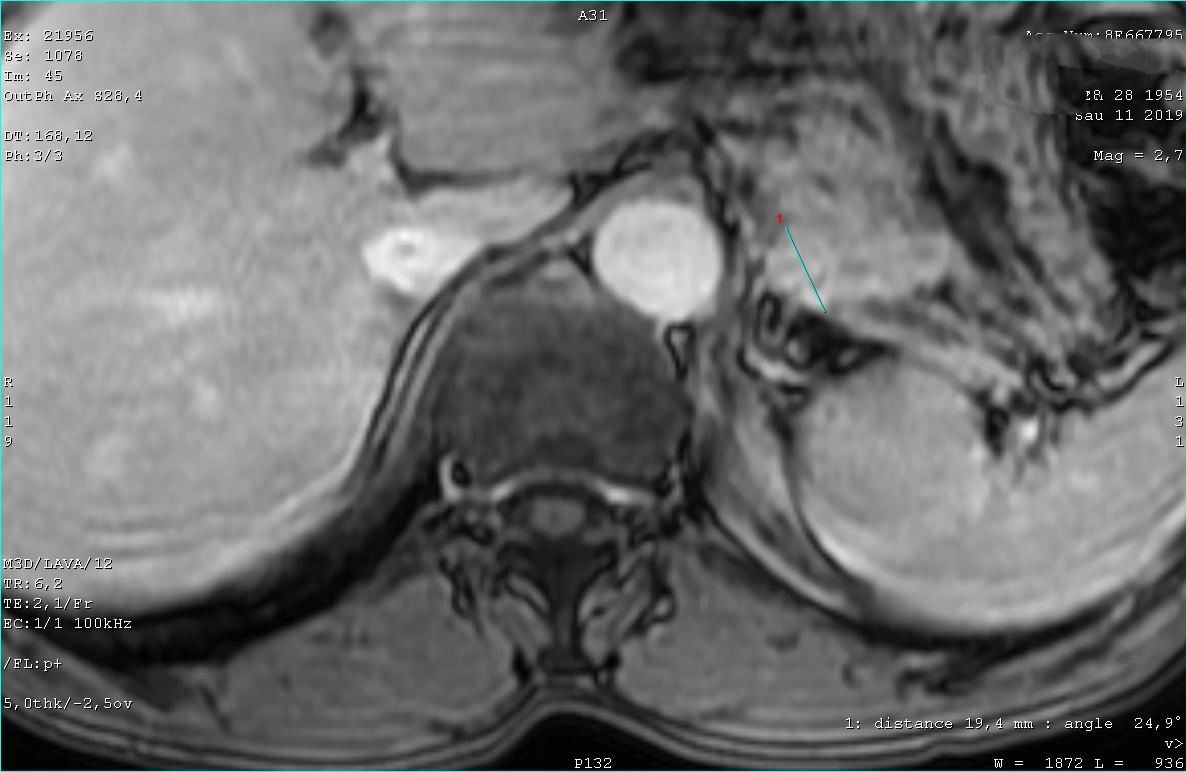

Опухоль хвоста панкреас

Пожилой мужчина. Жалоб не предъявляет.

Контрольное исследование через полгода - без динамики.

При повторном исследовании отрицательной динамики нет.